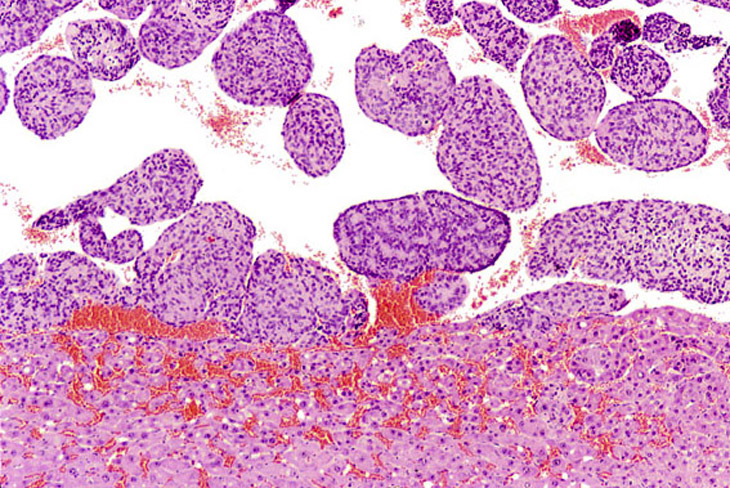

A small hepatoblastoma within an hepatocellular carcinoma. Non-neoplastic hepatic parenchyma is present in the upper right.